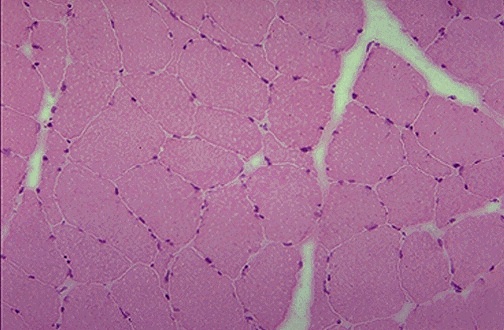

| At high power in cross section, normal skeletal muscle is seen to be composed of muscle fibers. Each fiber contains the contractile proteins: thick myosin filament interdigitating with thin actin filaments. The multiple nuclei of the fiber are at the periphery of the muscle fiber. |